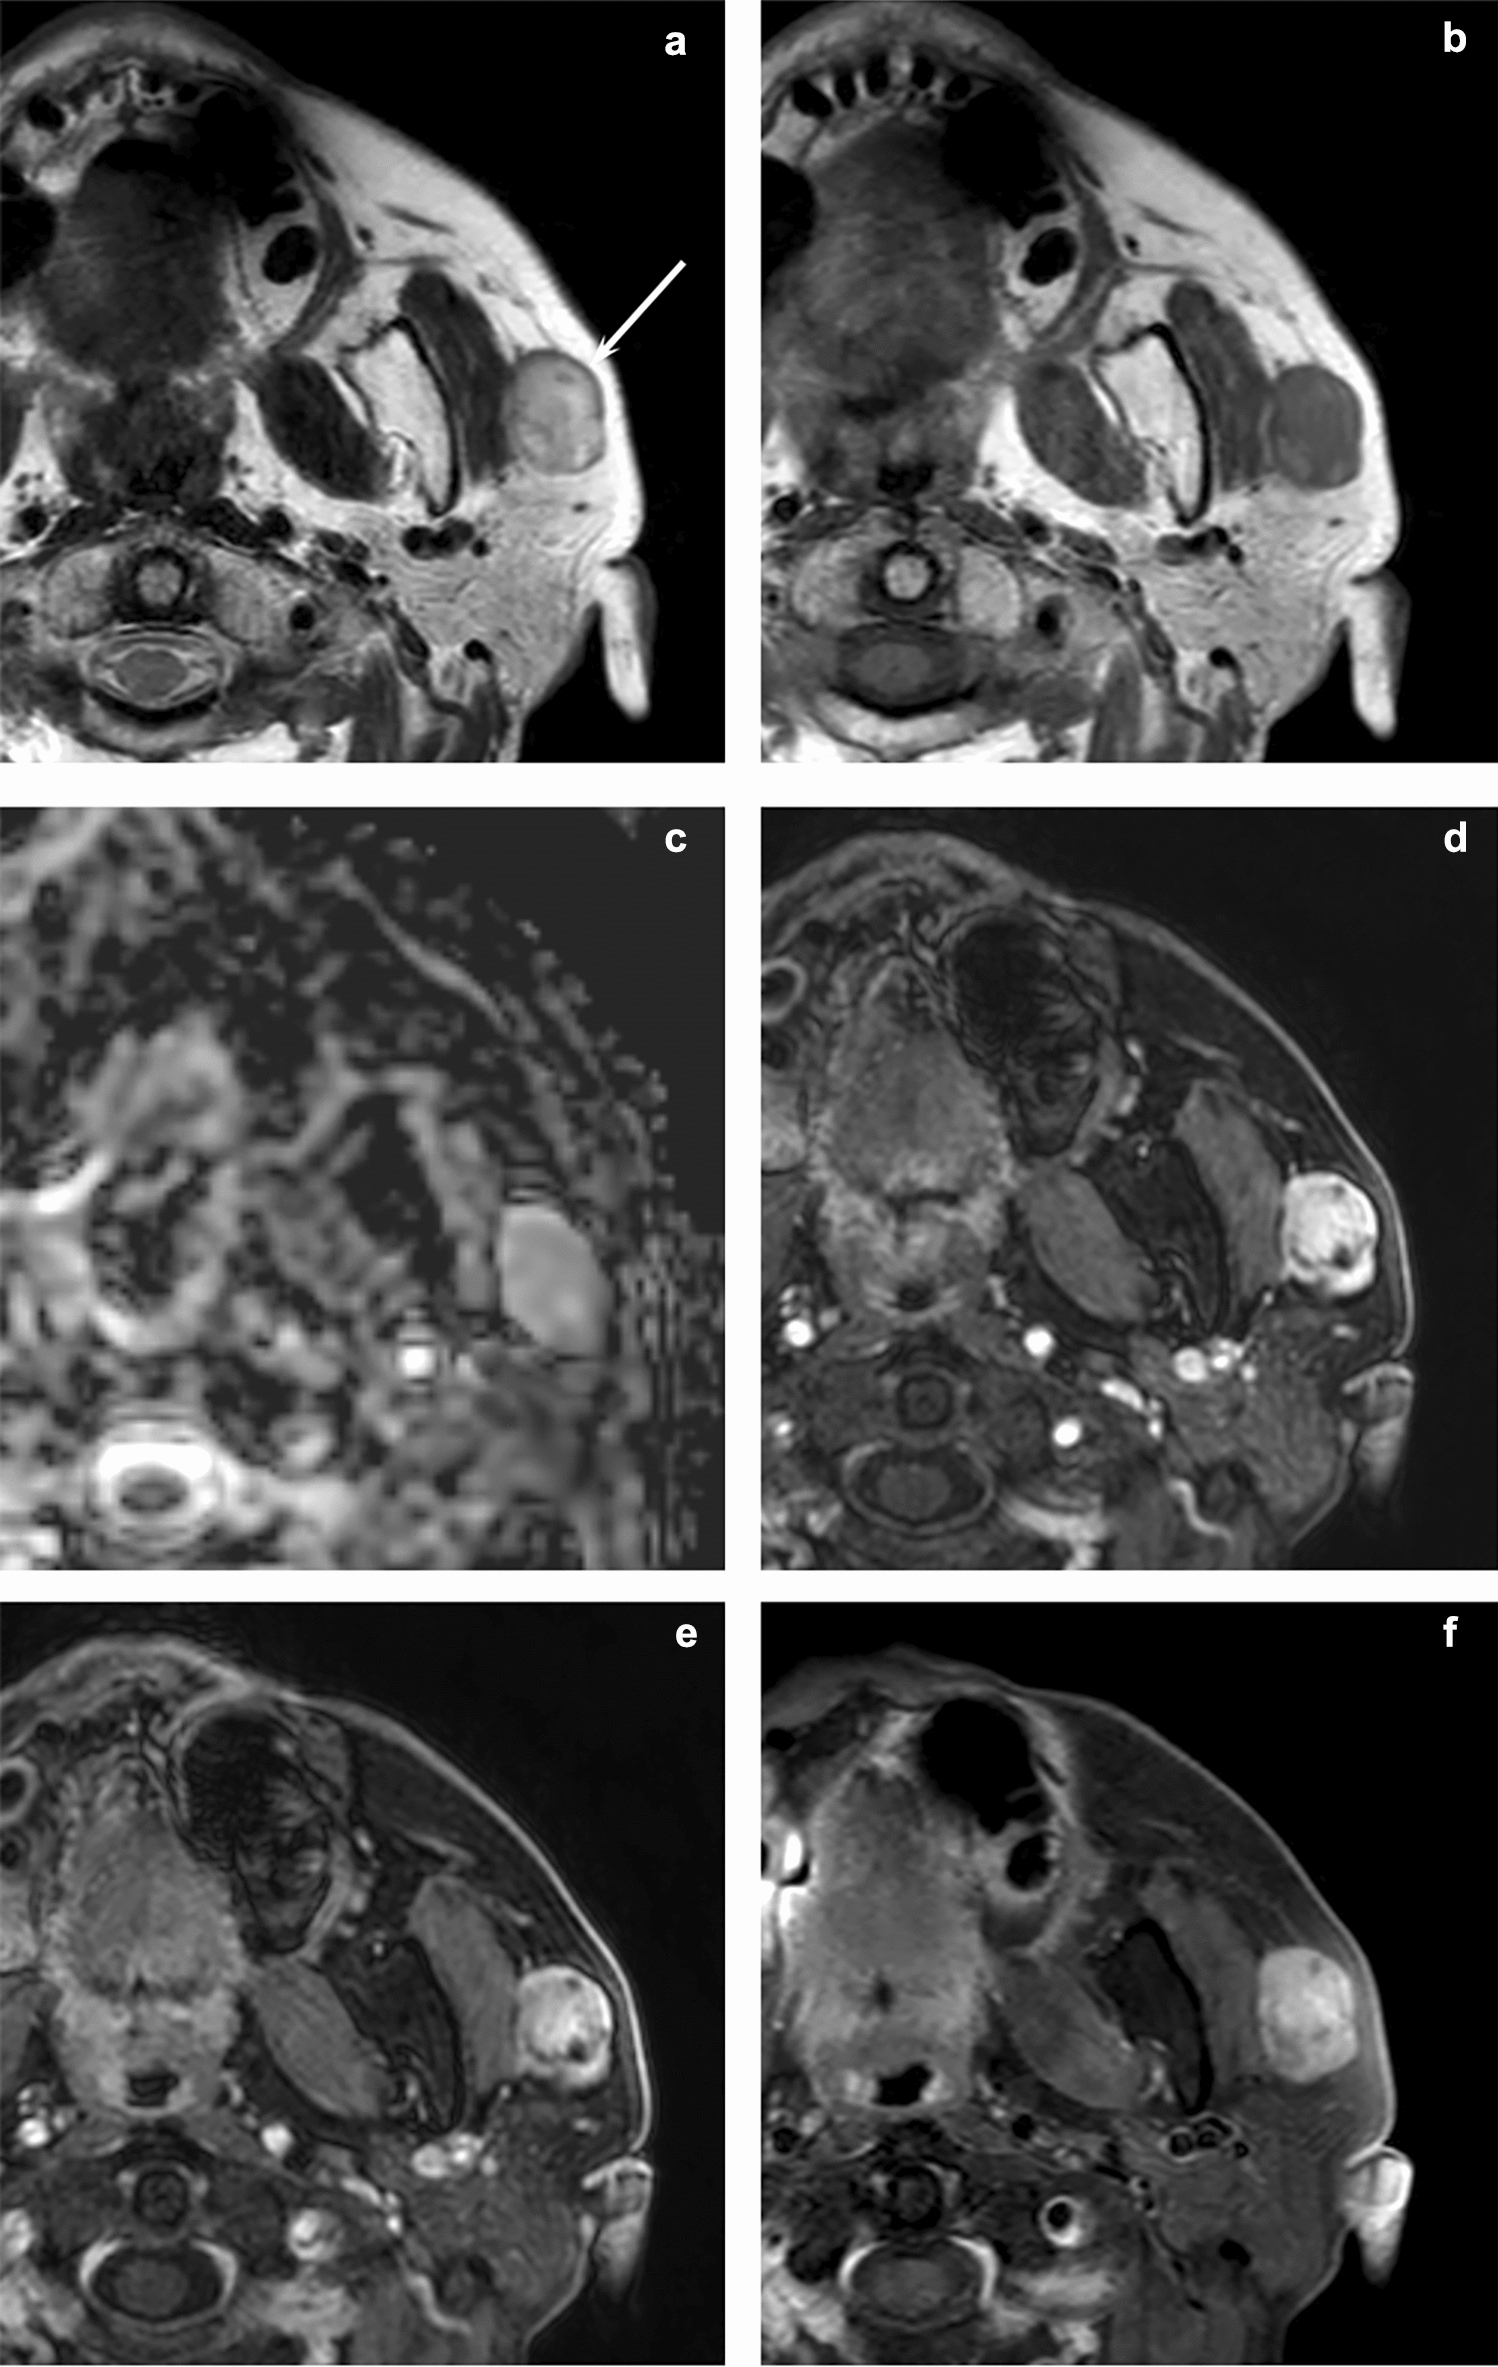

MRI and CT features of head and neck myoepithelioma: comparison with parotid pleomorphic adenoma

To evaluate the MRI and CT features of head and neck myoepithelioma in comparison with parotid pleomorphic adenoma. This r...

MRI features of histological subtypes of thyroid cancer in comparison with CT findings: differentiation between anaplastic, poorly differentiated, and papillary thyroid carcinoma

This study aimed to evaluate the MRI features of the main histological subtypes of thyroid cancer and enable differentiati...